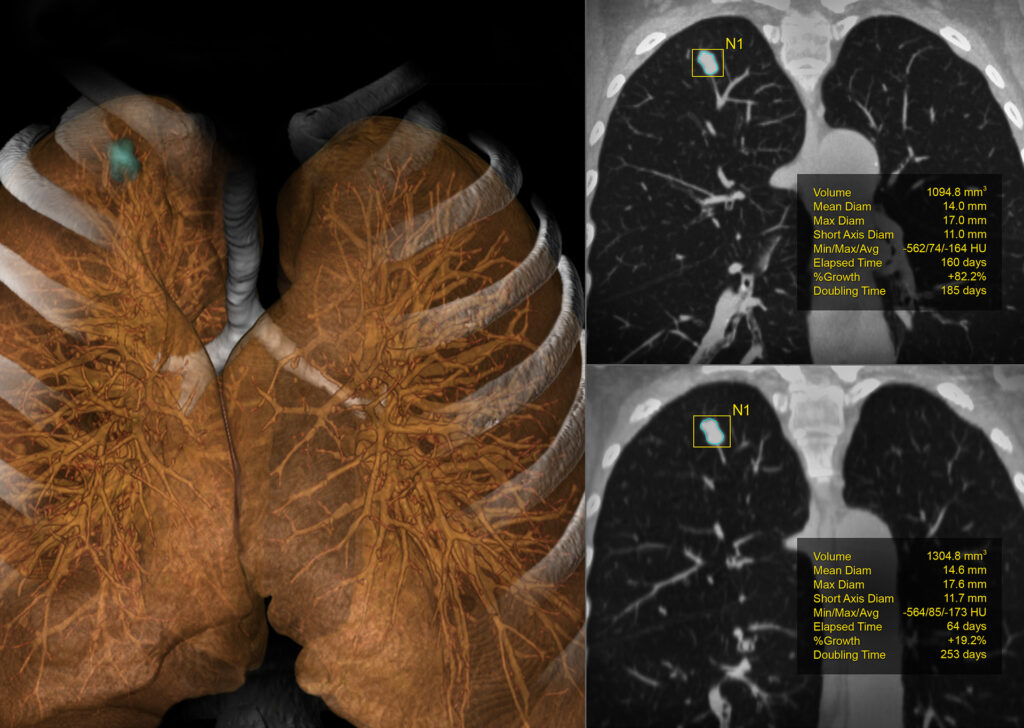

CT Lung Analysis

CT Lung Analysis aids in measuring and characterizing lung nodules. The interface and automated tools help to efficiently determine growth patterns and compose comparative reviews.

Visia™ CT Lung CAD

Visia™ CT Lung CAD is integrated into Vitrea® Advanced Visualization and facilitates time-efficient and safe radiological diagnosis of MSCT-images in clinical daily routine.